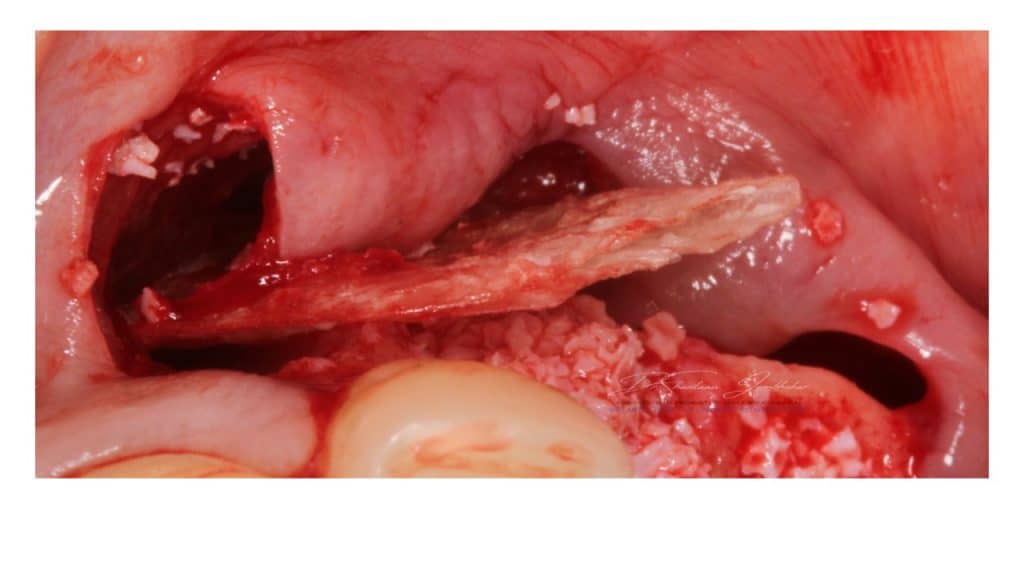

Buser Scrapper from Hu Friedy for harvesting autogenous bone. DBBM (BioOss) and Autogenous bone for GBR

Implant surface covered with autogenous bone scrappings

Second layer of Composite(Autogenous+xenograft 50:50 mix) layered

GBR membrane placed

GBR membrane covered with collagen fleece membrane